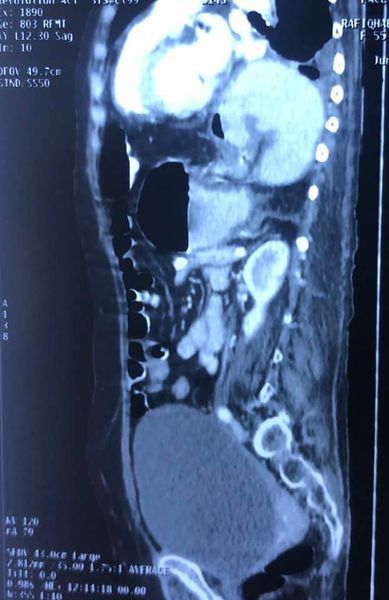

Challenging emergency during the COVID: Child’s A CLD with HUGE gastric varices uncontrolled

Child’s A CLD with HUGE gastric varices uncontrolled by Endoscopic glue and attempted EUS coiling. One salvage option would be TIPSS with balloon vascular occlusion but due to logistics we went for modified sugiura procedure. Splenectomy + Gastro esophageal devascularisation with anterior Gastrotomy and overseeing of gastric varices with pyloroplasty. Images show 1 CECT showing large gastric fundal varices. 2,3,4 Gastro Esophageal devasc 5, 6 Large fundal varices before and after oversewing. 7. Anterior gastrotomy 8. Pyloroplasty. Postoperative recovery was uneventful.